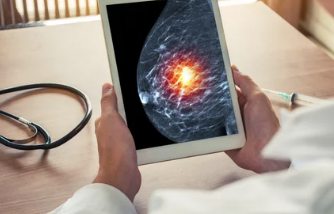

유방암은 조기 발견이 중요하기 때문에 정기적인 검진이 필요해요. 검진 방법에는 유방 촬영술, 초음파 검사, MRI 등이 있어요.

- 유방 촬영술 (Mammography): 유방을 압축해 촬영하는 방법으로, 미세한 종양을 발견하는 데 효과적이에요. 특히 40대 이상의 여성에게 권장돼요.

- 조기 발견 진단기기 개발: 인공지능(AI)을 이용해 유방암 초기 증상을 보다 빠르게 감지할 수 있는 진단기기가 연구되고 있어요. 정확한 진단과 조기 발견을 가능하게 해 주는 AI 기반의 유방암 검진은 의료계에서 큰 주목을 받고 있습니다.